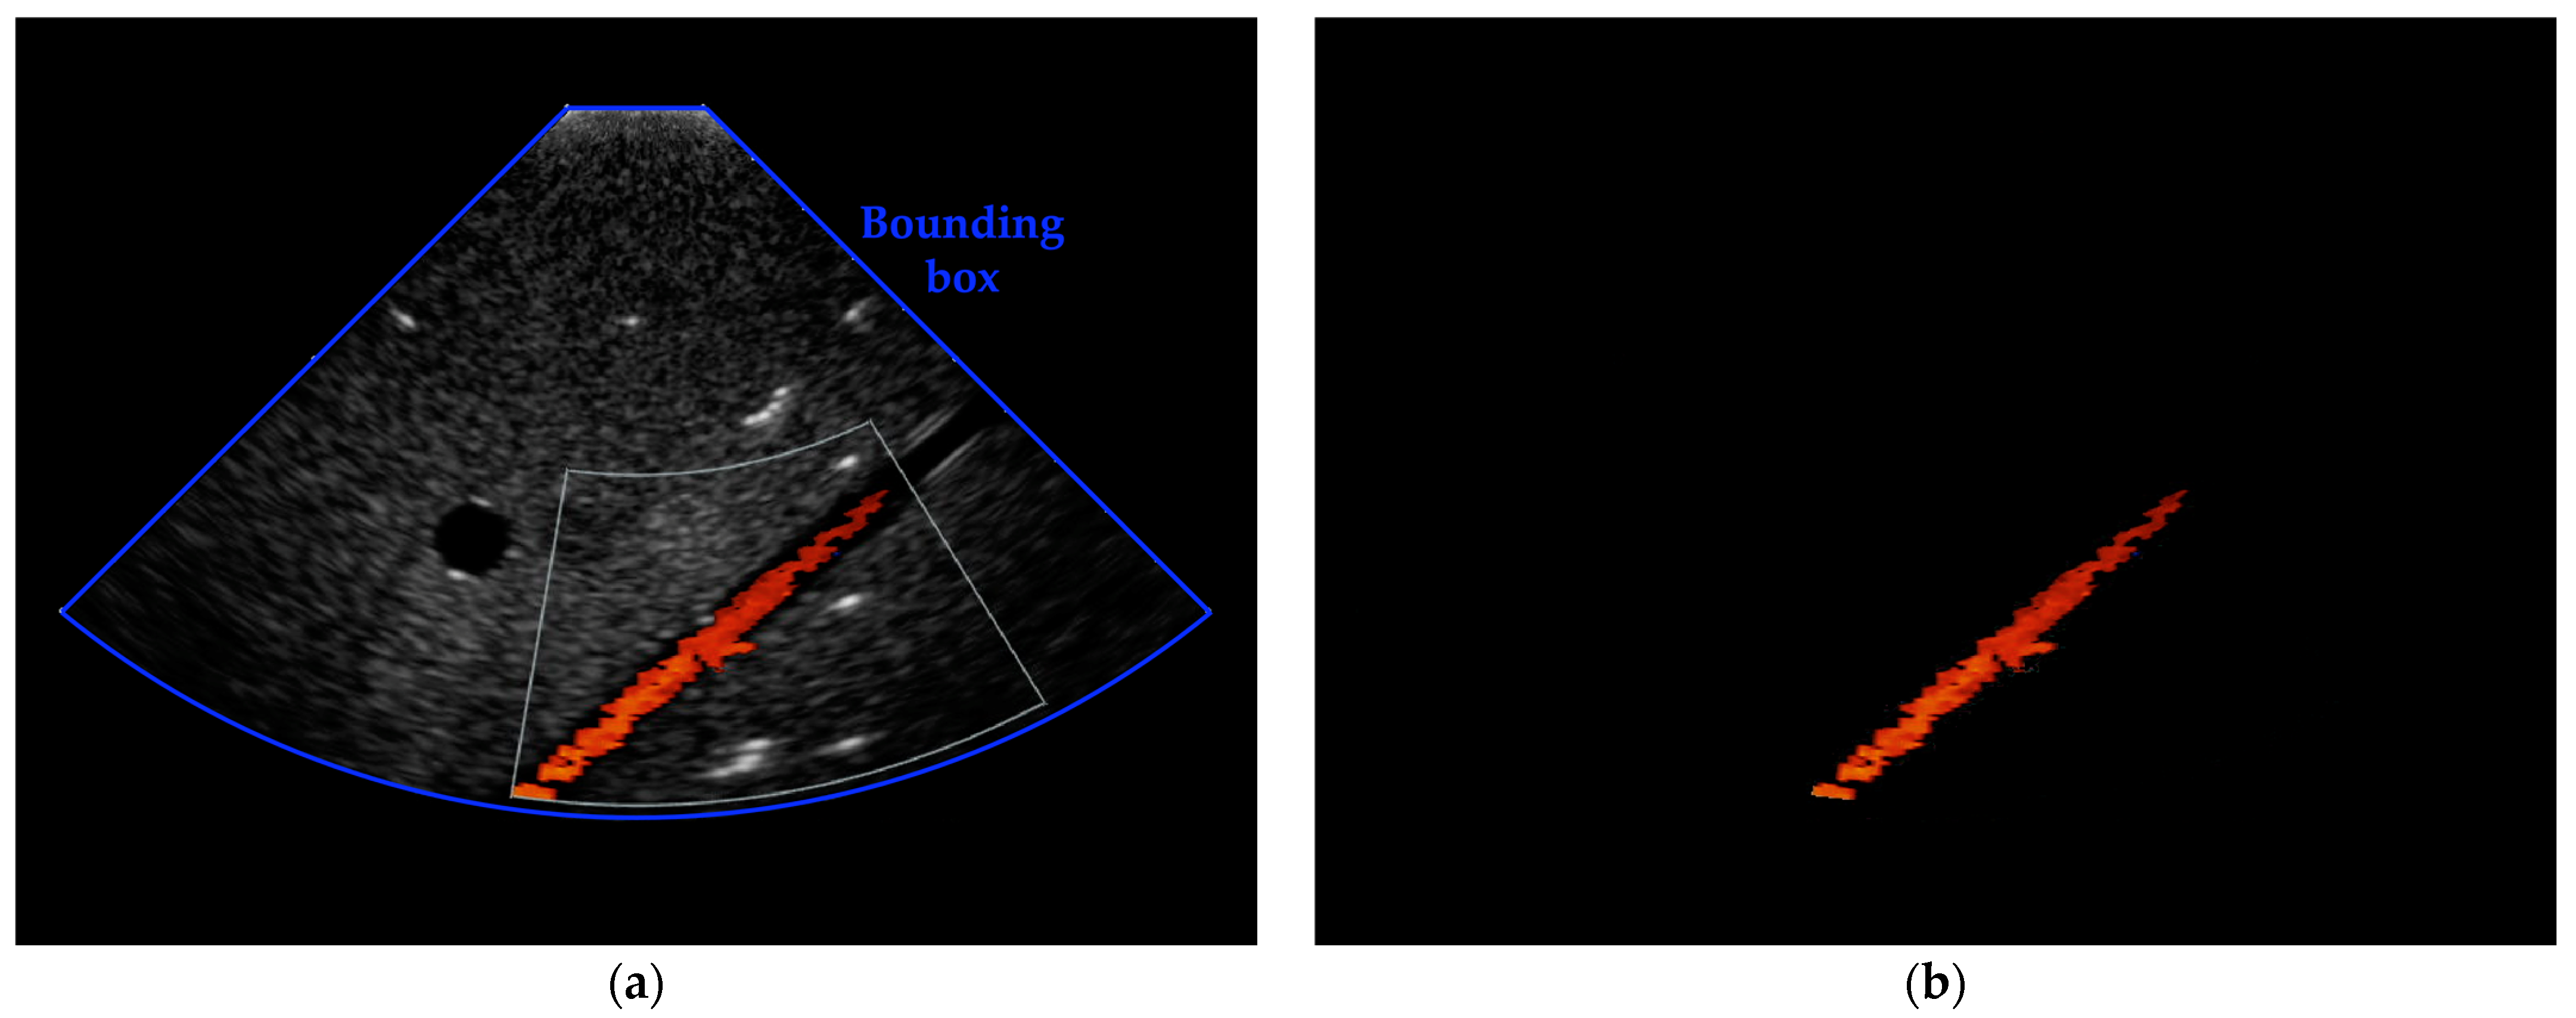

- a phased array probe to detect and display the CD signal;

- a US system for color Doppler imaging and data acquisition.